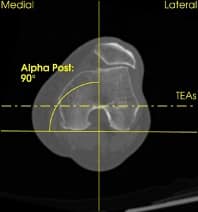

Ich verwende ein komplett neues System von der Firma Symbios. Dieser Kniegelenksersatz ist eine komplette Maßanfertigung. Es bedeutet, dass diese Knieprothese speziell nur für Ihr Knie angefertigt wird.

Ihr Knie wird zuvor genauestens ausgemessen und unmittelbar danach produziert. Es steht nach 6-7 Wochen für die Operation zur Verfügung.

- mehr Präzision durch 3D Planung

- an Ihr natürliches Knie angepasste Geometrie